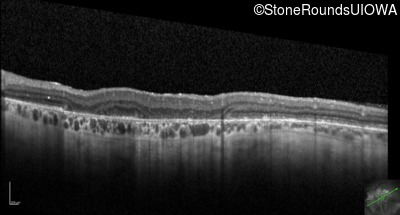

Optical Coherence Tomography - Right - 20/100 +1

Exemplar / OCT Stack